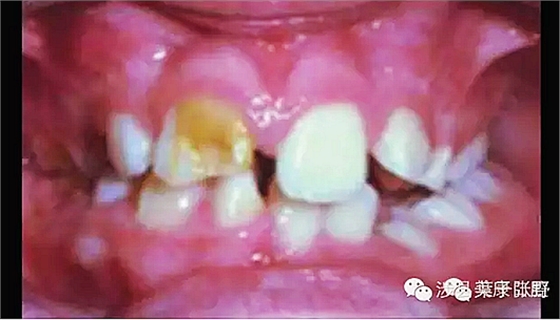

![SGTCU9W{CJ(KNO938]DJZ[Q.png SGTCU9W{CJ(KNO938]DJZ[Q.png](/Mobile/UploadFiles/FCK/2017-04/6362664285172919675298344.png_280.jpg)

影響咬合高度建立

會感染,嚴(yán)重者可以引起全身病變,危機生命。

牙根周圍頜骨腐爛吸收。